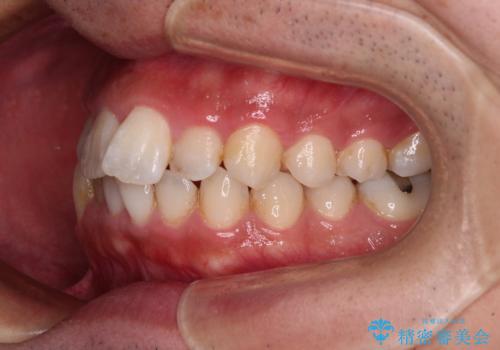

前歯のデコボコと突出感をマウスピース矯正できれいに

矯正治療後に銀歯をセラミックに替えたいとの要望があり、概ね歯列が整ったところで銀歯をセラミックに替え、仕上げにインビザライン1セットを使用して最終的に歯列を整えました。